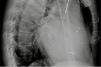

Via a subclavian vein approach, a 5F decapolar Response™ CSL electrophysiology catheter (Abbott) was used to create a three-dimensional (3D) model.1 After obtaining an endocardial shell the catheter was used to cannulate the coronary sinus (CS) (Figure 1). Under guidance by the electroanatomic system and very low dose fluoroscopy (to confirm that there was no catheter entanglement), a bipolar right ventricular (RV) lead was positioned in the RV apical septum. To continuously monitor the lead position (and identify possible lead dislodgment), the tip and ring poles were left connected to the EnSite system. The CS catheter was withdrawn and a sheath was used to catheterize the CS with the aid of the anatomic location on the 3D system. A guidewire (VisionWire; Biotronik) was inserted through the delivery system and connected to the EnSite system, and was used to map the anatomy and electrical activation of the CS branches (Figure 2). A branch was selected and the LV lead was placed in the latest site of ventricular activation (Figures 3 and 4). Using guidance by the navigation system and minimal fluoroscopy (hybrid approach), the right atrial lead was placed in a right appendage position, with real-time location of the other catheters (to check for possible displacement during manipulation of the atrial lead). Total procedure time was 96 min.

(A) Real-time visualization of catheter location (red arrow pointing to right ventricular lead, and yellow arrow to right atrial lead) and the VisionWire (Biotronik) inside the coronary sinus branches (white arrows); (B): electrical activation mapping of coronary sinus branches with guidewire and identification of the latest ventricular activation (mid segment of the lateral branch, dark blue).